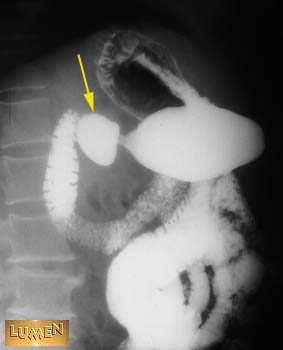

Question: Identify.

Answer

Duodenal bulb.